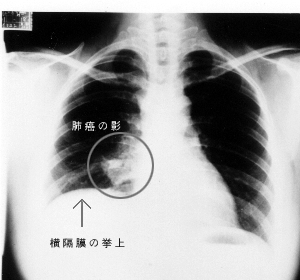

7、体检发现肺部阴影,局限于某肺叶、段的炎症,局部肺气肿或肺不张。